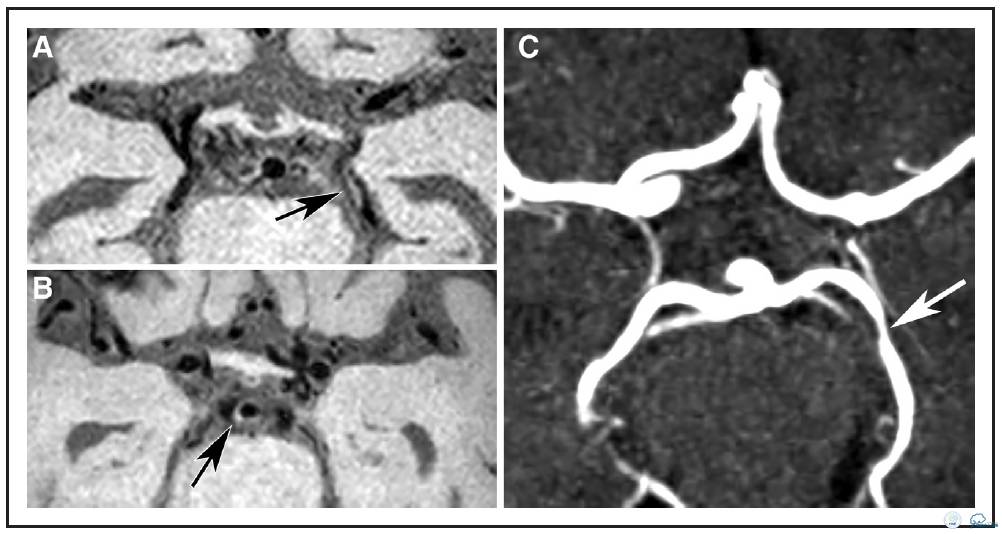

图1:72岁女性患者,左侧前循环梗死。A:横向各向同性的T1加权快速自旋回波采集容积重建图像。B:可见左侧大脑后动脉P2段偏心性,局部增厚病变(箭头),另外,可见基底动脉偏心,局部增厚病变(箭头B)不伴有管腔狭窄(箭头C)。C:横断面时间飞跃磁共振成象显示P2段同一位置为无症状血管壁狭窄病变。

分布、负荷和特征

18例患者(95%)存在颅内血管壁病变,15例患者存在多发病变。评估者间信度很高:组内相关系数为0.71,95%置信区间(0.196-0.920)。评价位置的评估一致性中等偏上,Dice相似系数Dice为0.57。494处受检节段中总共发现57处病变(12%),其中47处(82%)位于前循环(颈内动脉[ICA],n = 18;大脑中动脉[MCA],n = 27,大脑前动脉[ACA], n = 2),10处(18%)位于后循环(基底动脉[BA],n = 3 ;大脑后动脉[PCA],n = 7,见表2及图1)。57处病变中,25处(44%)注射造影后有强化(图2),43处(75%)为偏心性病变,14处(25%)为向心性病变,42处(74%)为局部增厚,15处(26%)为弥散增厚(表3)。在前循环斑块中,偏心病变同局部增厚存相关(图2,图I在线数据补充),向心病变同弥漫性增厚相关(P< 0.001)。19处病变(33%)为症状性病变(MCA病变;1例患者双侧病变),38处病变(67%)为无症状性病变。比较无症状和症状性病变时, 发现偏心性病变和无症状病间存在很大的相关性(P< 0.05)(无症状病变中有32处为偏心病变,占84%;症状性病变中有11处为偏心病变,占58%),但与强化或特定的增厚型式无关。症状性病变没有任何特定的形态特性。此外,MRA上显示正常或不规则的血管壁病变常为无症状病变,而MRA上显示狭窄的或闭塞病变是为症状性病变(P < 0.001;图2)。MRA显示的30处病变中:26处位于前循环,4处位于后循环。此外,MRA上显示的8处病变是在血管壁扫描序列上发现相应病灶。这些病变中,6处为不规则病灶,1处是狭窄病灶(图3),另1处为不规则且闭塞病灶。两处狭窄病灶同时也是症状性病灶。